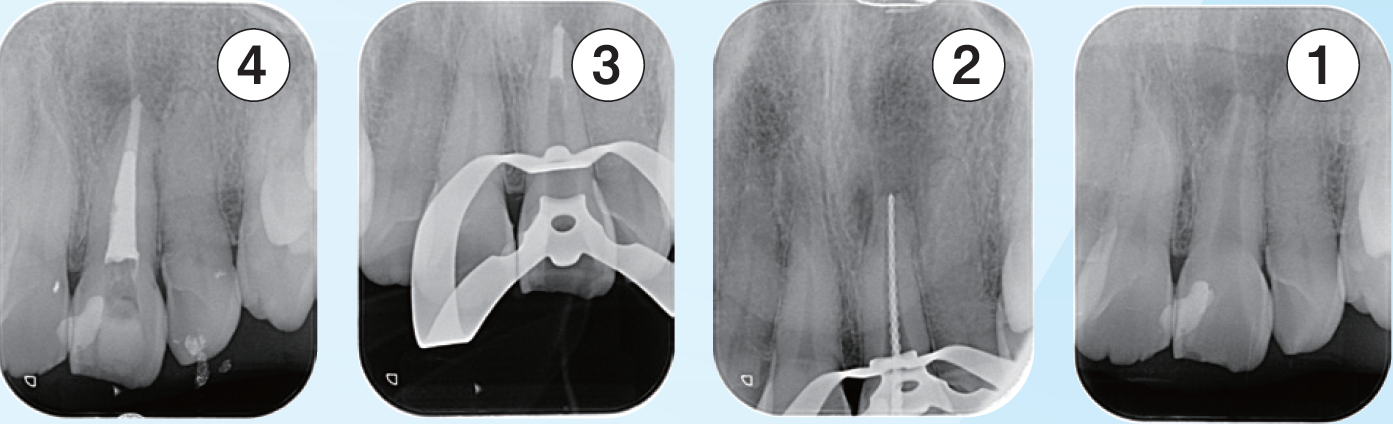

臨床症例3 その2

左上2番の感染根管処置

根中間部は狭窄しており根尖までは穿通障害歯である根中間部で異物を触知したため除去を行なった右は 、除去した破折ファイルを示す

臨床症例3 その3

①根管内の異物除去後のレントゲン像

②根中間部は狭窄しているものの細い号数のテーパーの少ないファイルで根尖までファイルを到達せせることができたのでEMRを測定しレントゲンを撮影した

③根尖は吸収度は少なく根尖孔径は#30で形成しガッタパーチャとMTAシーラーを用いて根管充填した

④根管充填後3ヶ月のレントゲン像

根尖周囲に見られた透過像の改善傾向が認められる

臨床症例3 その4

左上1番の根尖部にMTA製剤充填時のCBCT像

唇側皮質骨は大きく開窓し、根尖病変の大きさが鼻腔底付近まで広がっていることが確認できる

臨床症例3 その5

術後1年のCBCT像

根尖周囲に見られた根尖病変はほぼ消失し、唇側皮質骨の開窓も改善したことが認められる